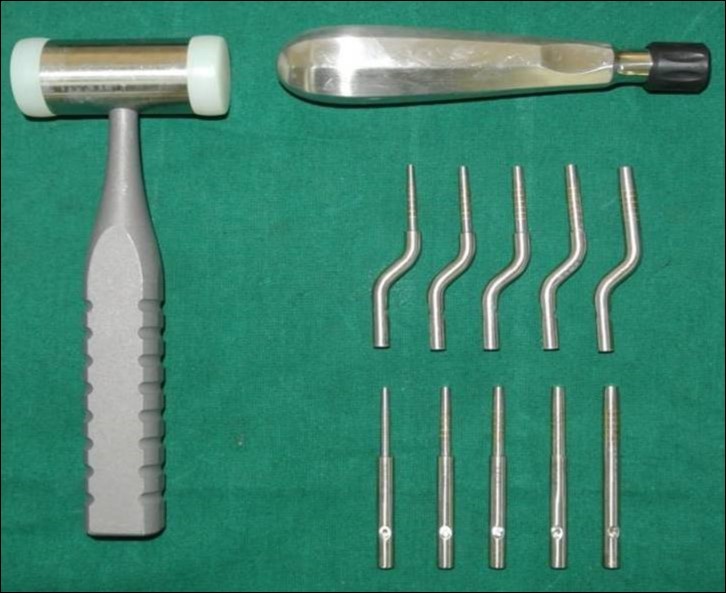

A total of 20 sinus augmentations were carried-out in 17 patients satisfying the criteria (inclusion and exclusion) requiring placement of implants in atrophic maxilla and in other situations of anatomic constraints. The patients were informed about the study including the use of the synthetic graft material and their approval was sought before their inclusion into the study. A written consent was obtained from each of the participating patient. After a detailed history and a thorough clinical examination, including systemic and regional/local examination, patients were taken-up for the sinus augmentation. The type of sinus augmentation procedure, direct or indirect, was decided based on the pre-operative residual bone height evaluated radiographically. The residual bone height was recorded using CBCT scans and a computer based software where the measurements were made from the crest of the ridge till the sinus floor lining. Apically tapered, commercially pure titanium implants (Life Care Devices Private Limited, Mahim, West Mumbai, India) (Figure 1a,b) were used with sinus osteotomes (Figure 2) and associated reamers (Figure 3). The length of implants used were 8, 10 and 11.5mm while the diameter used were 3.5, 4.0 and 5mm. The graft material used was calcium phosphosilicate (CPS) putty (Nova bone dental putty, Novabone products, Alachua, Fla) (Figure 4) in quantities ranging from 0.5cc to 2cc. It is a pre-mixed moldable material consisting of four components including two bioactive phase components, a 55% standard CPS particulate and a 14% CPS smaller particulate in addition to 12% polyethylene glycol additive phase and 19% glycerine binder phase. Bioactivity is initiated immediately upon implantation. The smaller CPS particles release calcium and phosphorous ions into the area while the binder material gets absorbed over a period of a week exposing the larger CPS particulates to blood. In calcium phosphosilicate, the particle sizes are in micrometer size range of 90-710 micrometer range, irregular, in both size and shape. According to Moore et al, in 2001, bioactive glass granules are more quickly reabsorbed than hydroxyapatite, thus, allowing a much more precocious new bone formation in the repair of bone defects.7 On them, osteoblasts show several cytoplasmic processes, pseudopodia, compact appearance, and disorderly dorsal surface, which is characterized by a high cell membrane activity. Therefore, as to the adhesion and close contact between osteoblasts, bioactivity is considered crucial to the development of new bases for bone tissue bioengineering. Its use in various fields, due to its excellent biocompatibility and its physical and chemical properties, has encouraged studies on the feasibility of implant coating, so as to obtain better biologic fixation, and also as a carrier of osteo-inductive substances such as bone morphogenic proteins and other growth factors.8, 9 Other authors also demonstrated the effectiveness of bioactive glass as they improved the osseo-integration of coated implants providing better bone support and presenting with an increased stability when compared to the machined implants.10

Figure 1.(a,b) Apically tapered, commercially pure titanium implants (Life Care Devices Private Limited, Mahim, West Mumbai, India).